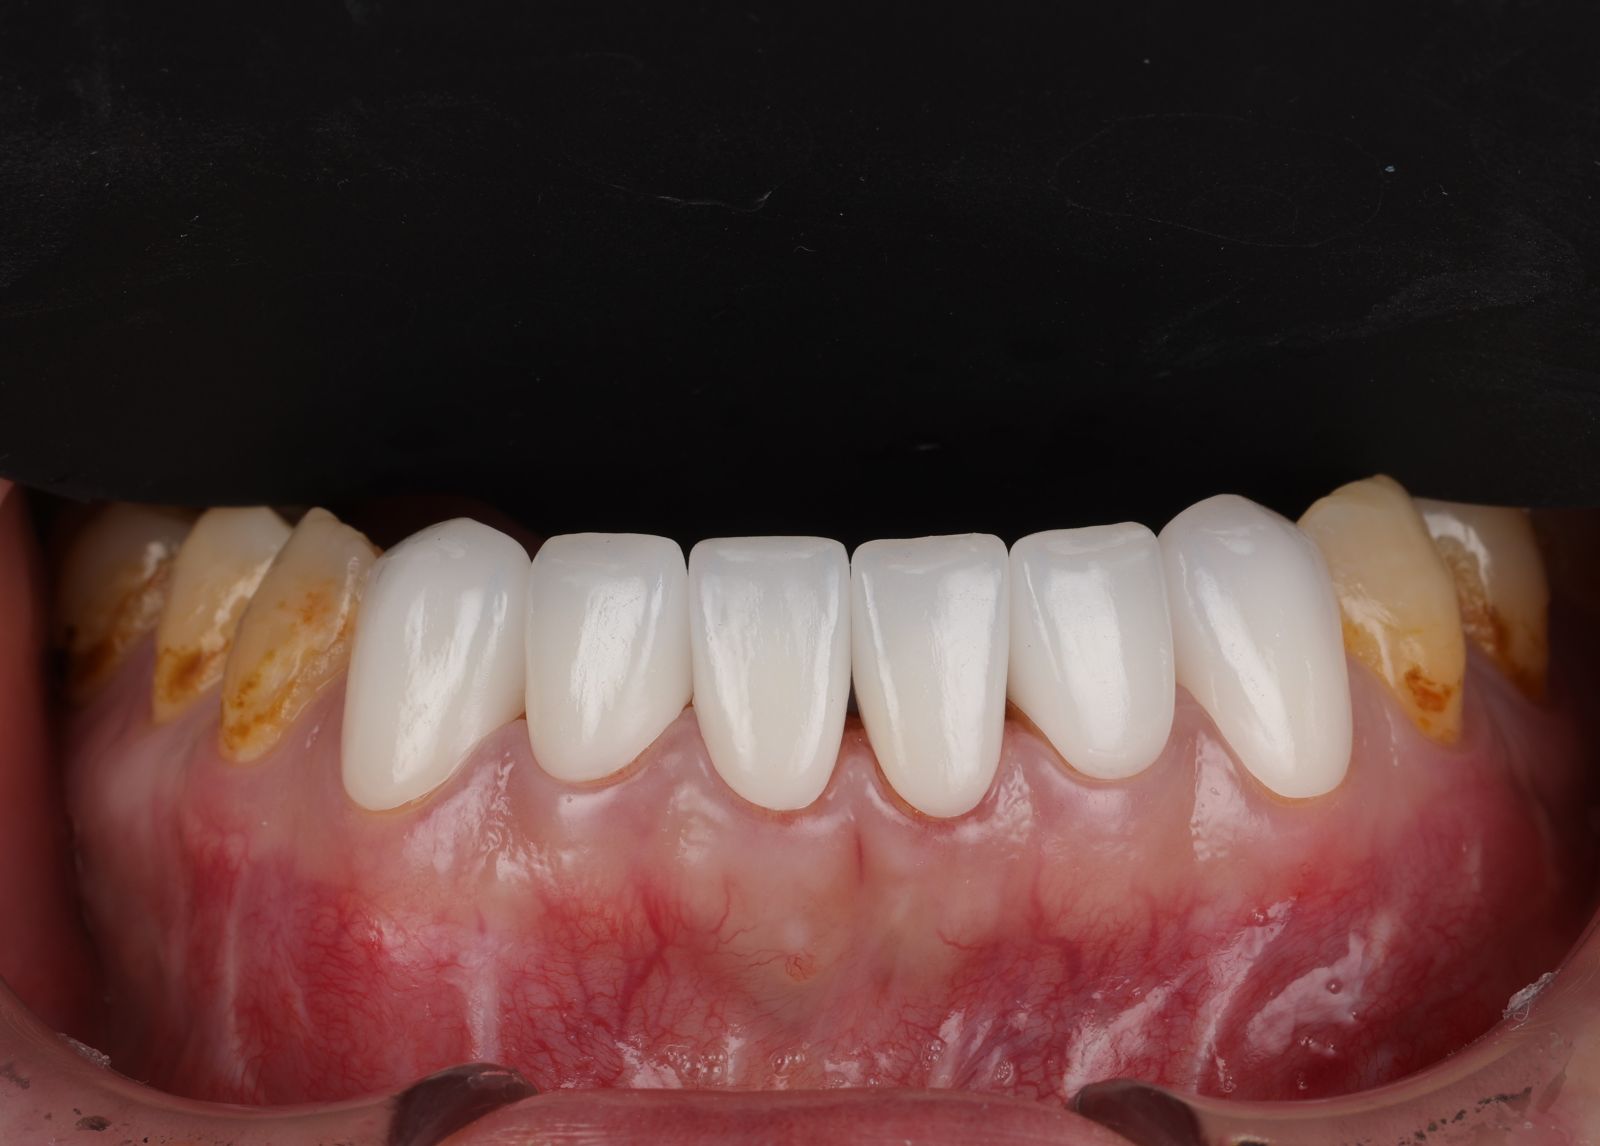

希望牙齒前牙區能一致變白,型態上也希望能調整得更自然,跟醫生討論之下決定把笑容區6顆牙齒都一起做前牙美學,用全瓷冠搭配美白貼片一起處理!

經過數位微笑曲線設計,選擇自己喜歡的色階後就可以製作適合自己的美學全瓷牙囉!全瓷冠經過特殊處理呈現的通透感,讓牙齒白而自然透亮。